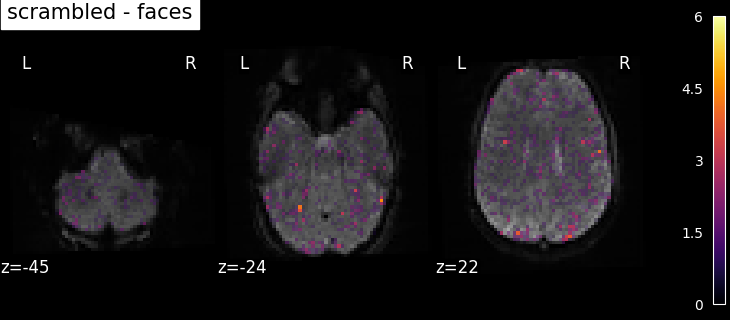

To get more interesting results out of the GLM model, contrasts can be computed between regressors of interest. The nilearn.glm.first_level.FirstLevelModel.compute_contrast function can be used for that. First, the contrasts of interest must be defined. In the spm_multimodal_fmri dataset referenced above, subjects are presented with ‘normal’ and ‘scrambled’ faces. The basic contrasts that can be constructed are the main effects of ‘normal faces’ and ‘scrambled faces’. Once the basic_contrasts have been set up, we can construct more interesting contrasts like ‘normal faces - scrambled faces’.

The activation maps from these 3 contrasts is presented below:

../_images/sphx_glr_plot_spm_multimodal_faces_002.png ../_images/sphx_glr_plot_spm_multimodal_faces_003.png ../_images/sphx_glr_plot_spm_multimodal_faces_004.png